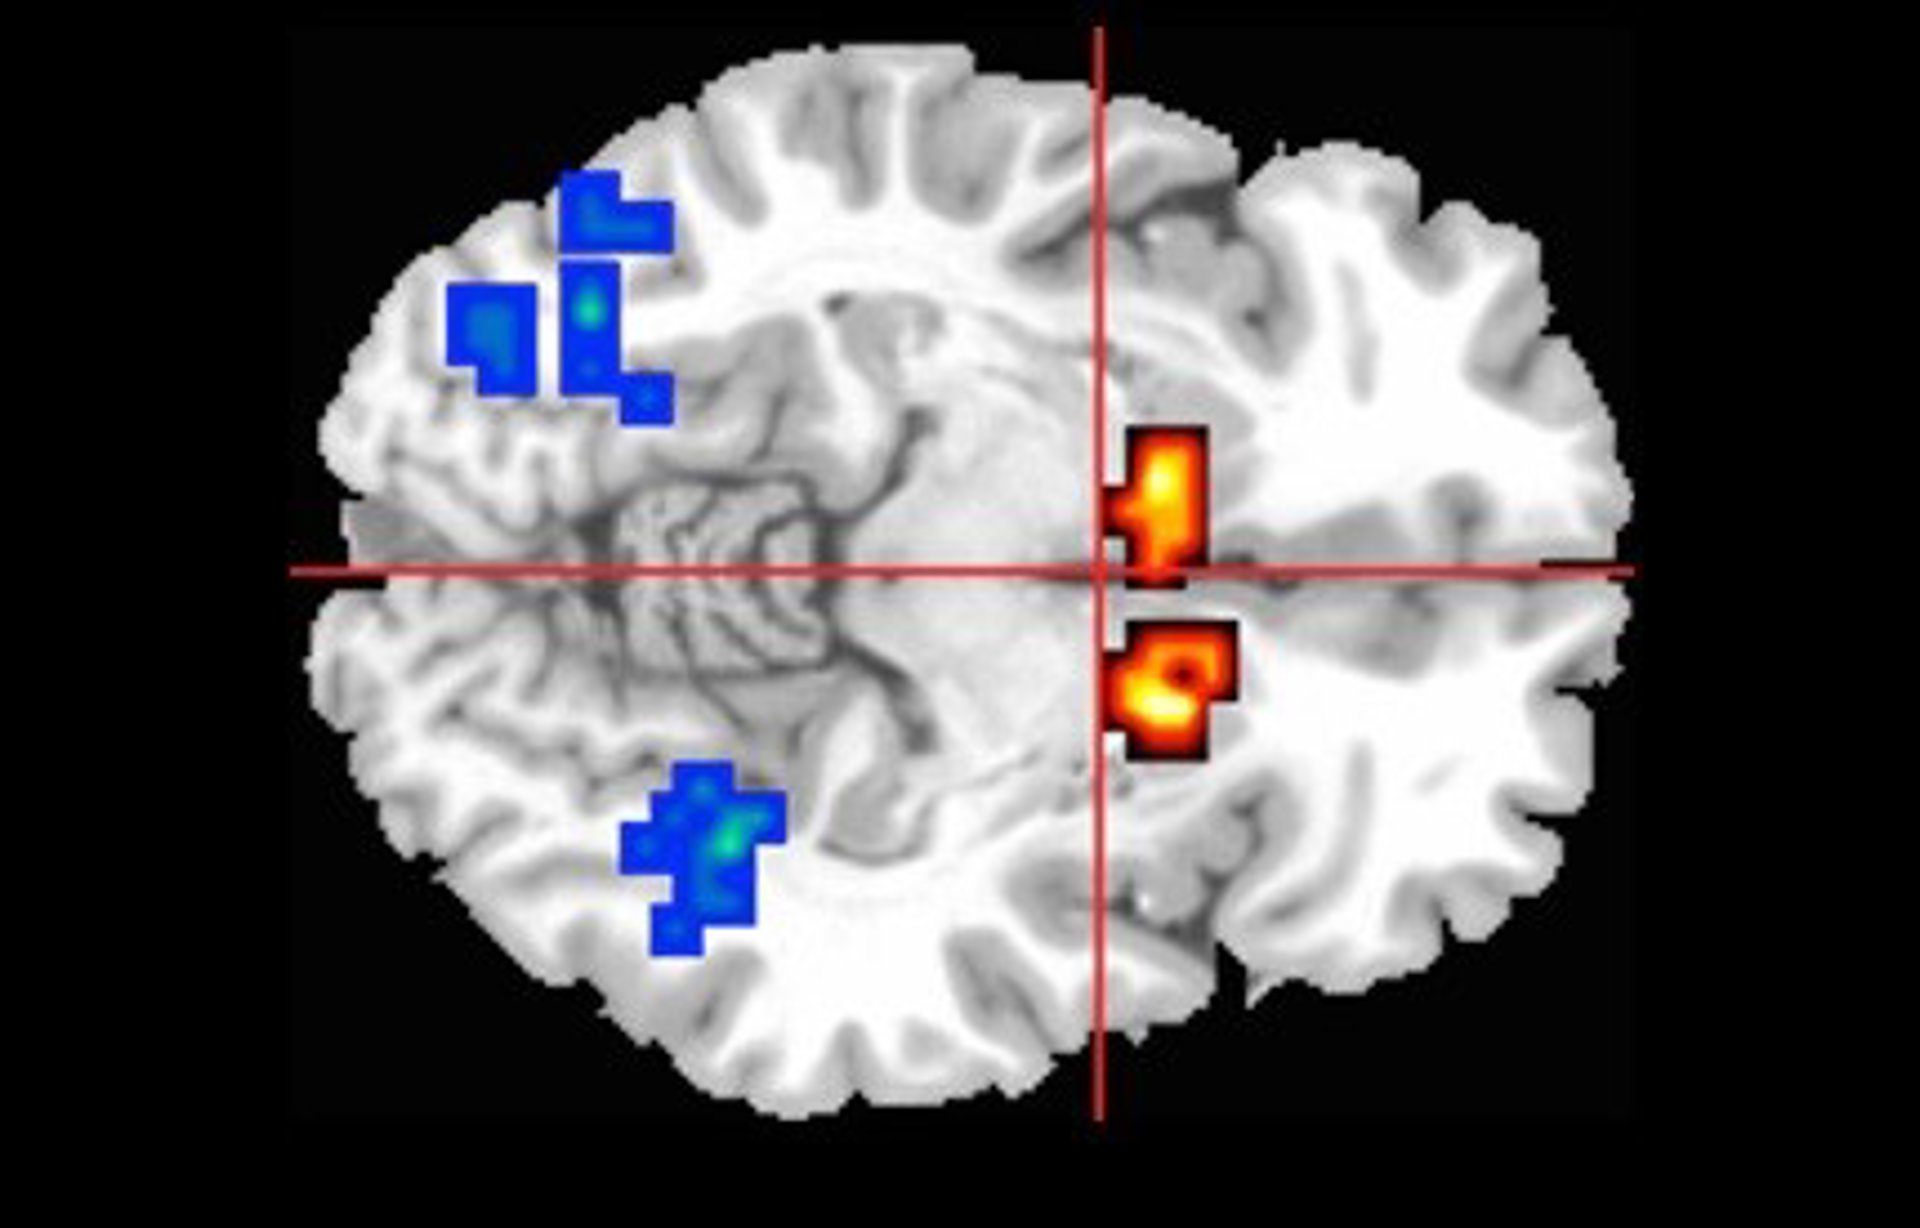

Archivo - Áreas Afectadas Del Cerebro En Personas Con Psicosis

Archivo - Áreas Afectadas Del Cerebro En Personas Con Psicosis - KING'S COLLEGE LONDON - Archivo